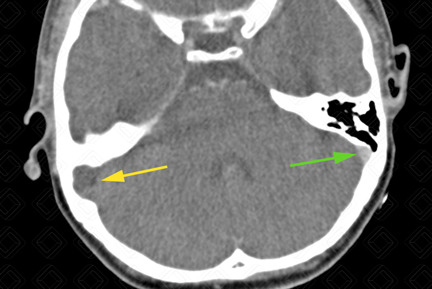

Texto alternativo para a imagem Figura 2. Créditos: Dra. Elazir Mota - Rio de Janeiro/RJ

Descrição da figura 2: Essa solução de continuidade posterior determina trombose do seio sigmoideo direito (seta amarela). Observe o seio sigmoideo esquerdo bem opacificado (seta verde).

Descrição geral das imagens: Complicação de otite média crônica com mastoidite e evolução para trombose de seio venoso (figuras 1 e 2).